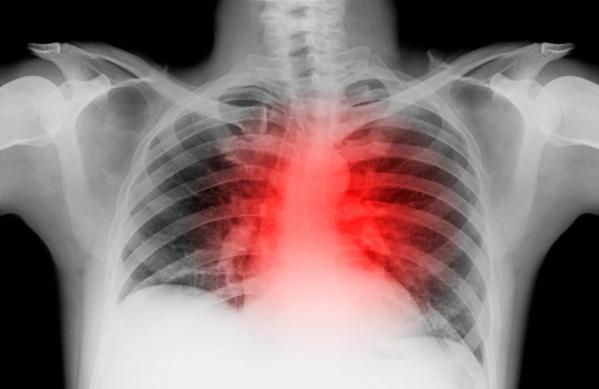

X-ray of lung with heart attack

A new study has shown that a Cleveland Clinic-developed protocol significantly improved the chances of in-hospital survival among patients who experience the most severe type of heart attack (STEMI), and reduced door-to-balloon time, a key factor in the treatment of STEMI, for all patients, regardless of socioeconomic factors.

Heart disease is the leading cause of death in the United States and worldwide, and STEMI, a life-threatening type of heart attack that is caused by a sudden and prolonged blockage of the blood supply to the heart, is a primary cause of death in patients with heart disease.